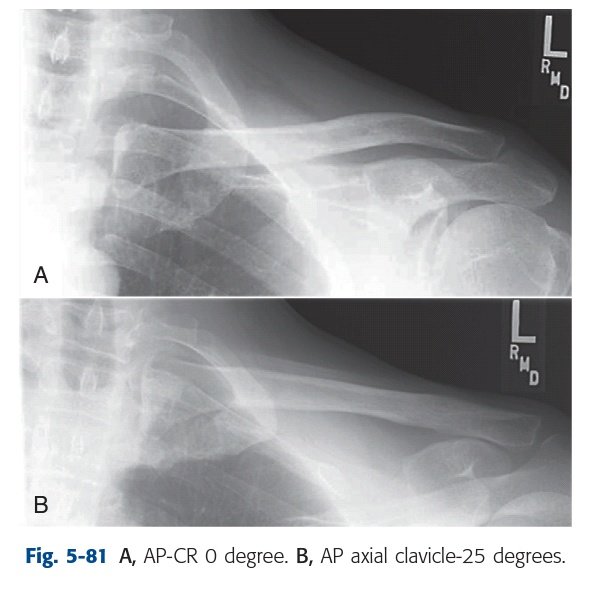

☆فحص عظمة الترقوة

☆clavicle " collar bone"

•تأخذ شكل الحرف S.

•هي أول العظام تكلساً (تبدأو الجنين بعمر ٥-٦أسابيع)*

•وآخر مراكز التكلس اكتمالاًوذلك في عمر (٢٢-٢٥سنة)*

•تعد العظمة الطويلة الوحيدة التي تأتي بشكل أفقي.

•تستخدم كمرجع في كثير من الفحوصات الإشعاعية:

اوضاعها:

وضعان رئيسيان:

AP(0 angle) and AP axial ( 15 ° to 30 ° cephalad ).

وعادة يعملان سوياً في بعض الأقسام.

▪وضع المريض:

واقف أو مستلقي.

▪مركز الشعاع:

منتصف عظمة الترقوة.

▪تعليمات:

أخذ نفس عميق ثم حبس النفس، وهذا يساعد في رفع العظمة لأعلى.

فائدة وضع AP axial

انه يرفع الترقوة بعيداً عن scapula.

تعتمد الزاوية على حجم جسم المريض كلما كان نحيفاً احتجنا لعمل زاوية أكبر.

لذا دليل أن الزاوية عملت بشكل مناسب

(نقد الوضع):

تكون الترقوة فوق scapula

وفوق الضلع الثاني و الثالث.

فقط جزء من medial متراكب مع الضلع الأول و الثاني